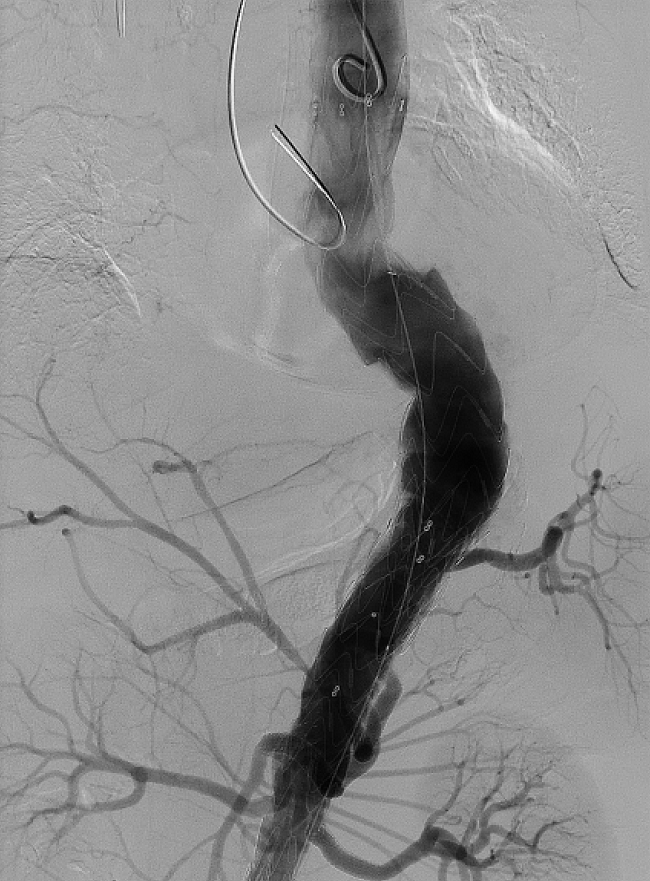

▲ 术后造影:瘤体隔绝,内脏分支血管血流通畅

在手术麻醉科主任胡强夫、医生郭佩垒的配合下,王兵教授带领血管外科崔文军主任、安乾副主任、任菲副主任医师、王梦宇医师向这一高难度手术发起挑战。凭借丰富临床经验及精准介入手术技能,在杨先生的左上肢、腹股沟部行穿刺,通过造影实时确认胸腹主动脉瘤位置。在DSA监视屏监测及导丝的引导下,王兵教授团队成功将体外开窗的覆膜大支架精确植入到动脉瘤部位,并将覆膜小支架超选置入内脏4分支腹腔干动脉、肠系膜上动脉、双侧肾动脉内,从而将血流与薄弱的瘤壁隔绝,不仅消除了瘤体破裂、出血隐患,还保留了内脏分支血流的通畅,防止胃肠道、肝胆胰脾、双肾等重要脏器的缺血现象。经过长达5个小时尽心尽力、一丝不苟的操作,王兵教授团队成功拆除了这颗不定时“炸弹”,杨先生转危为安。术后两周CTA复查提示“胸腹主动脉瘤隔绝效果佳,内脏动脉支架通畅”,恢复效果良好。